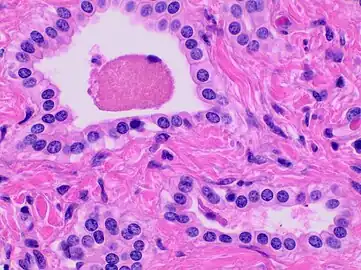

Histopathology of a bile duct hamartoma, high magnification, H&E stain. It shows typical features of bile duct hamartoma: